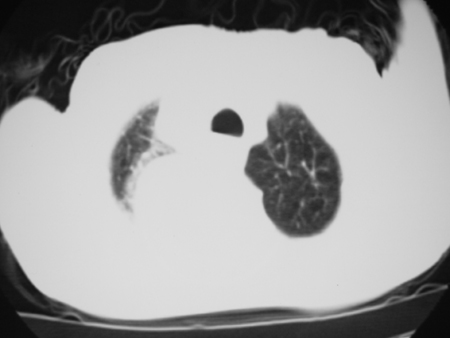

标题: CT24778:肺部病变

男77岁,胸痛就诊

右侧胸腔积液,部分包裹,右下肺膨胀不全,右下肺感染。

考虑右肺门占位并下叶不张 右胸包裹积液

右肺中叶及下叶炎症并胸腔积液(部分包裹),建议抽液后复查ct除外占位。